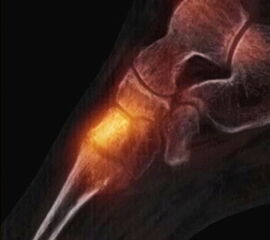

In Abbildung 3.4. ist ein typisches Beispiel für ein symptomatisches Os trigonum dargestellt.

Zum Lesen der Bildbeschreibung und zur Vollansicht bitte das Bild anklicken. Bild: H. C. Rischke